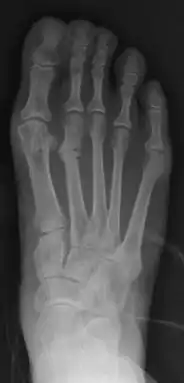

| Stress fracture of the second metatarsal bone | |

March fracture is the fracture of the distal third of one of the metatarsals occurring because of recurrent stress. It is more common in soldiers, but also occurs in hikers, organists, and people whose duties entail much standing (such as hospital doctors). March fractures most commonly occur in the second and third metatarsal bones of the foot.[1][2][3] It is a common cause of foot pain, especially when people suddenly increase their activities.[4]

X-ray is seldom helpful, but a CT scan and an MRI study may help in diagnosis.[5] Bone scans are positive early on. Dual energy X-ray absorptiometry is also helpful to rule out comorbid osteoporosis.[6]